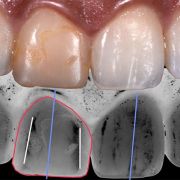

A single central incisor would render your smile unpleasant. Restoring such a case is a challenge per se. Understanding of the color physics and most importantly "HOW DO WE SEE WHAT WE SEE !!" is the key of success.

A single faulty restoration in one of the centrals could change your smile

The two centrals is the window of smiles' beauty!

Perfect shade is not the only factor for success. Shape, angulation and line angles are of great importance.